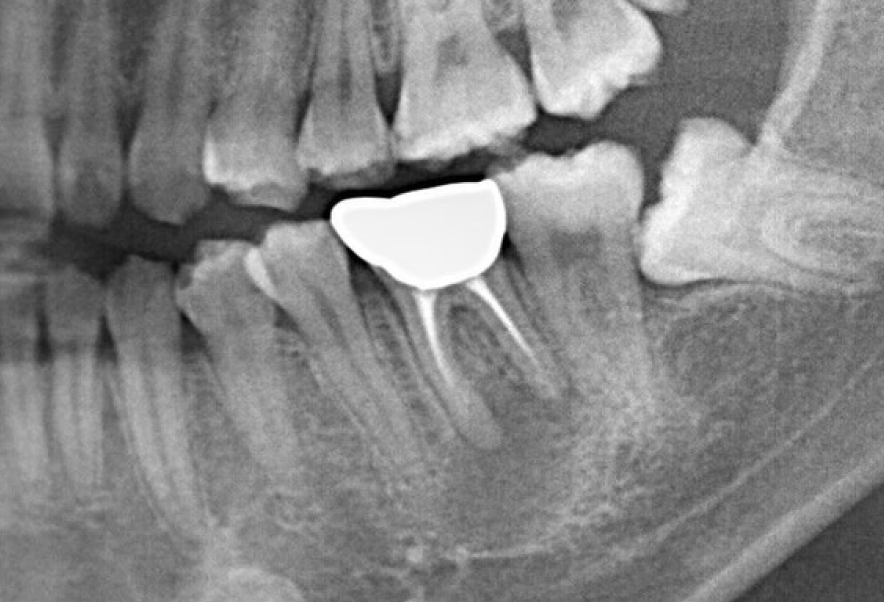

Before

After

他院で根管治療後、膿んできた歯の再治療